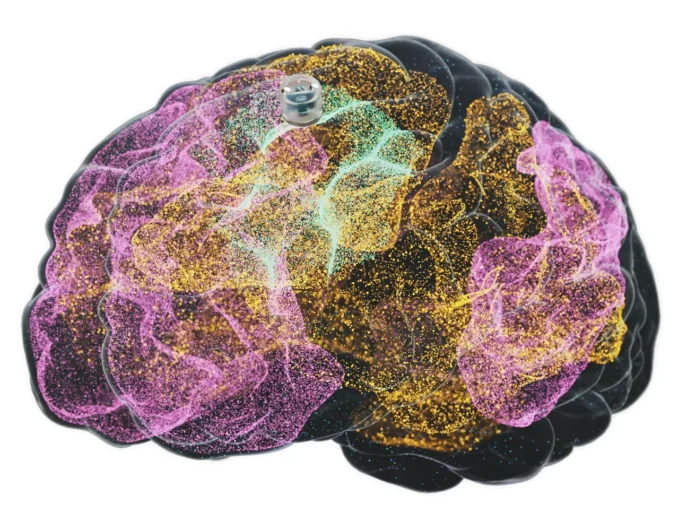

Geliştirilen cihaz, yaklaşık bir yaban mersini büyüklüğünde küçük bir implant olarak tasarlanıyor. Kafatasına, beynin koruyucu zarı olan dura materin üst kısmına yerleştiriliyor. Bu sayede daha derin beyin bölgelerine girilmeden, daha az invaziv bir çözüm ortaya çıkıyor.

İmplantın hedefinde, beynin bilişsel kontrol ve karar verme süreçlerinde rol oynayan “central executive network” yer alıyor. Depresyon yaşayan bireylerde bu ağın aktivitesinde düşüş gözleniyor. Cihaz, bu bölgeyi elektriksel olarak uyararak sinir ağları arasındaki iletişimi güçlendirmeyi amaçlıyor.